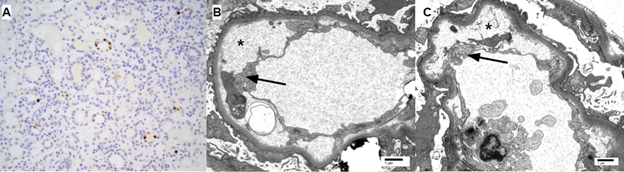

Case report: A 48-year-old man with end stage kidney disease secondary to diabetes mellitus underwent a 4 HLA-mismatched, deceased donor renal transplant from a 40-year-old donor who died of a cerebrovascular accident. Cold ischemia time and warm ischemia time were 31 and 18 minutes respectively. CMV IgG was positive in donor and negative in recipient. Intravenous methylprednisolone and antithymocyte globulin were used for induction for anticipated delayed graft function. He was discharged on postoperative day 6 with a serum creatinine (SCr) of 8.1 mg/dL.. His allograft function continued to improve, achieving a SCr of 1.67 mg/dL at 1-month post-transplantation. His SCr had since fluctuated between 1.4-1.7 mg/dL. At 4-month post-transplantation, he was found to have low grade BK DNAemia (900 copies/mL) managed with mycophenolate dose reduction alone. He did well until 14-month post-transplantation when he presented with non-oliguric AKI with a SCr of 15.6 mg/dL (baseline 1.5 mg/dL) requiring dialysis initiation. Peripheral smear demonstrated thrombocytopenia but no schistocytes. A renal allograft biopsy (figure 3) was performed which demonstrated BK nephropathy, TMA, and no evidence of rejection.Labs revelaed CMV DNAemia of >140,000 copies/ml and BK DNAemia of 17,000 copies/ml. Donor-specific antibodies, HIV RNA polymerase chain reaction (PCR), hepatitis C RNA PCR, anticardiolipin antibody, stool shiga toxin PCR, and stool and blood cultures were all negative.